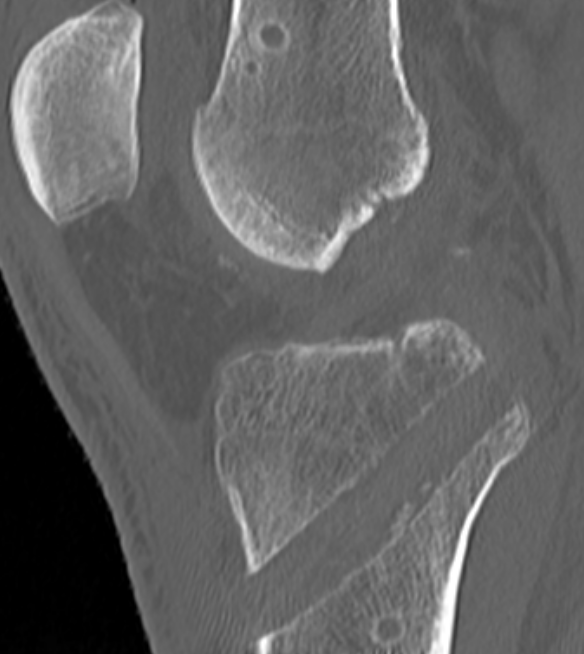

2. Displaced bony avulsion fracture

1. Repair bony avulsion

Repair Bony Avulsion

Options

Open posterior approach

- posterior approach

- Burks modified posterior approach

Arthroscopic